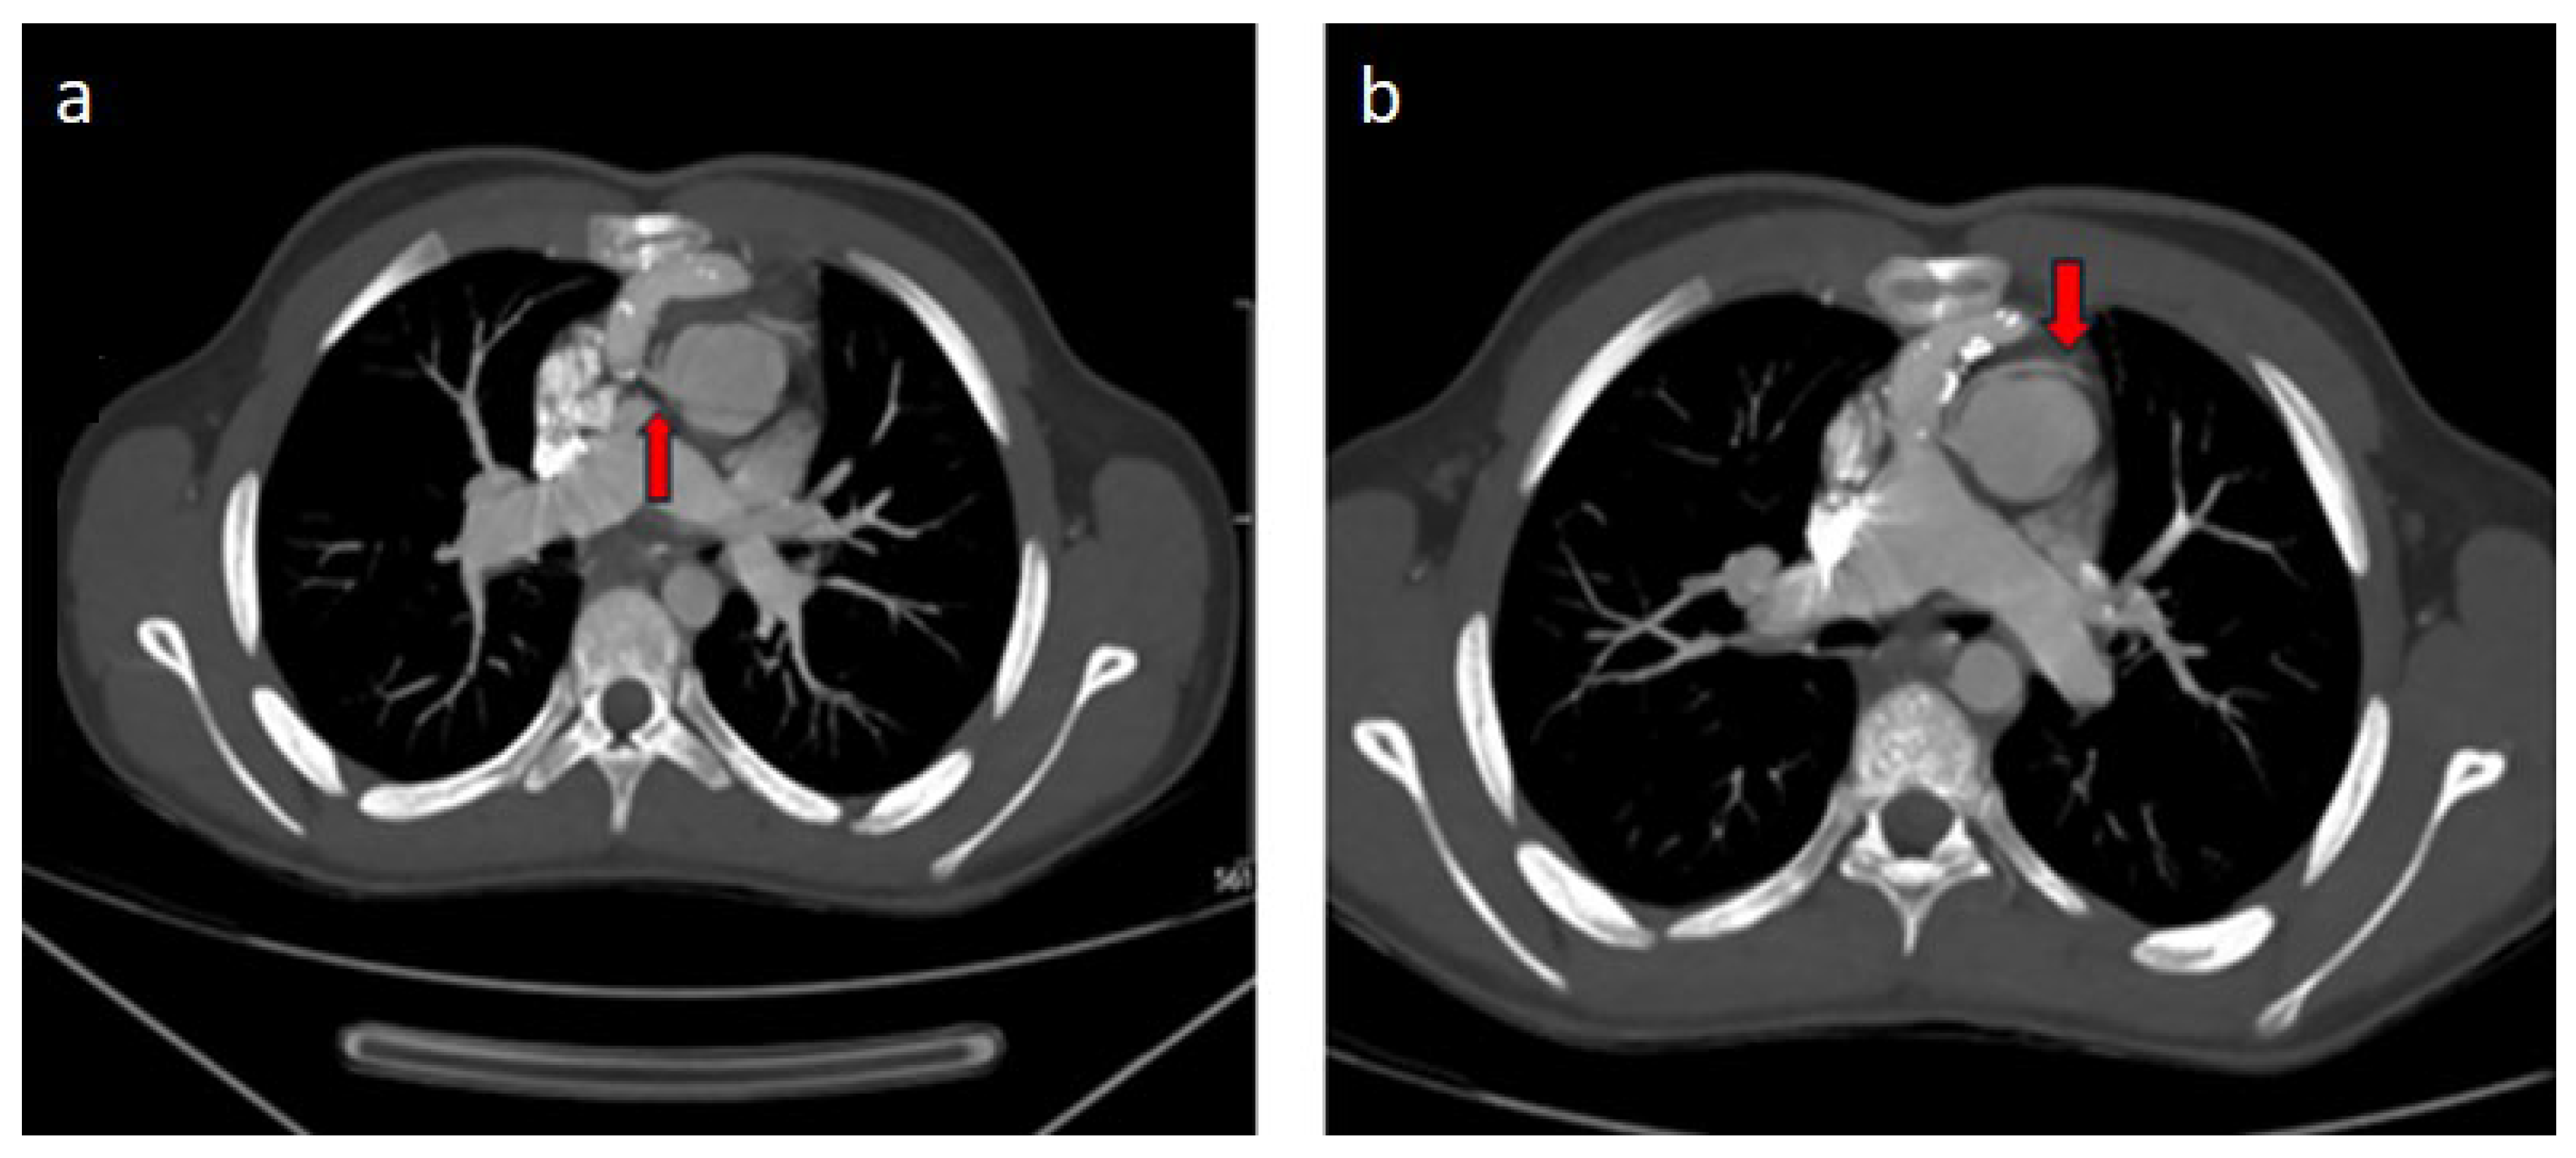

| Operated TGA (arterial switch) | Cx separated from the right coronary artery |

| Operated TGA (Rastelli) | Left coronary artery with interarterial course separated from the right coronary sinus |

| Single ventricle morphology (Fontan) | Cx leaving the right coronary sinus |

| Operated aortic stenosis, pulmonary stenosis (ROSS) | Left coronary artery leaving the right coronary sinus |